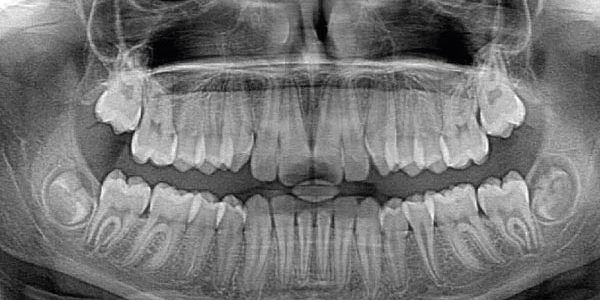

Ortopantomografia

La Ortopantomografía o también llamada radiografía Panorámica, es un tipo de radiografía extra-oral en la que aparecen Maxilar, Mandíbula , dientes y Articulación Temporo- Mandibular.

Es una radiografía en dos dimensiones en la que se aprecian los dientes, sus tejidos de soporte y estructuras anatómicas adyacentes.

- La Ortopantomografía, sirve para realizar diagnósticos de patologías dentales, tales como Agenesias, Quistes radiculares, Periimplantitis, Periodontítis, Caries…. y Estudios Ortodónticos.

El aparato para realizar la Ortopantomografía, gira a través de la cabeza emitiendo una radiación y es así como capta la imagen de toda la boca y mandíbula.

- Es un elemento esencial para el diagnostico del dentista , sobre todo en una primera visita, puest que así se tiene un conocimiento en conjunto de toda la boca.